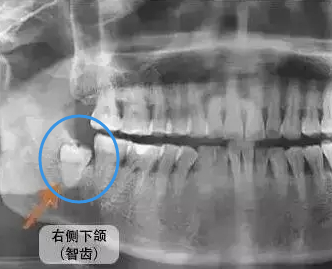

3、有智齒位置不正,經常發炎等,建議先拔除智齒後矯正比較好,這樣可以避免矯正後智齒對於(yu) 牙列的擠壓,造成畸形複發的情況。